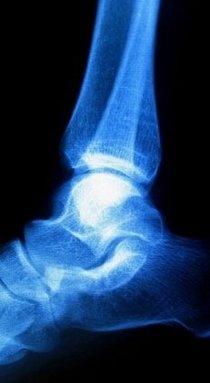

If you are suffering from Haglund’s deformity you will most likely have noticed a bony enlargement at the back of the heel. This inflammation is caused when the soft tissue around the Achilles tendon becomes irritated. Irritation at this particular spot is often the result of pressure caused by the back of pump-style shoes. Other signs of Haglund’s deformity include pain in the back of the heel, where the Achilles tendon and the heel meet, swelling in the back of the heel and redness or inflamed tissue at the site of the swelling.